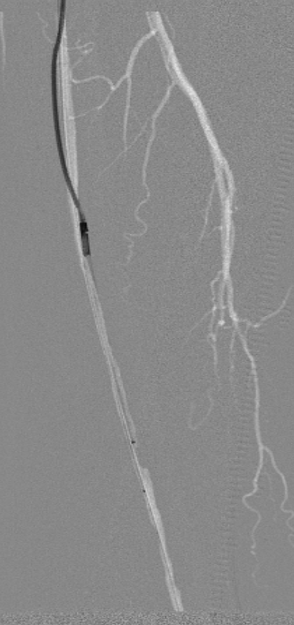

图为:导丝通过病变 置入保护伞 使用Turbohawk定向旋切

图为:股总动脉珊瑚礁病变定向旋切结果股浅动脉段尚未完成定向旋切